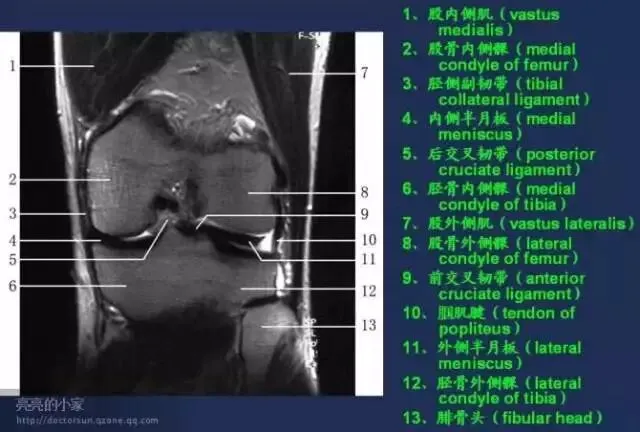

收藏!全身MRI解剖图谱,医生必备